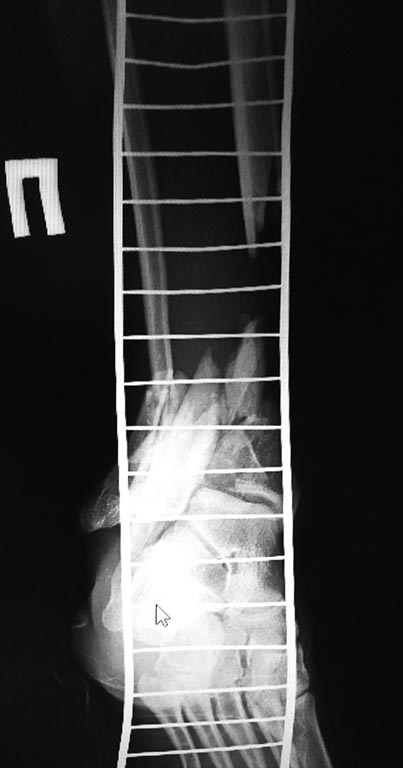

Представляю вам снимки первичные при поступлении и голень в аппарате на сегодняшний день. Тактическое предложение следующее:

1 вариант, учитывая скомпрометированную суставную поверхность б/берцовой кости, выполнить ретроградно штифтом артодез с фиксацией перелома б/берцовой кости. Выполнить рассверливание и открыто не вмешиваться.

2 вариант) микрохирурги предлагают открыться на место перелома б/берцовой кости, удалить нежизнеспособную кость и выполнить трансплантацию м/берцовой кости с другой голени , на сосудистой ножке. Предложите свой вариант возможного оперативного вмешательства. Буду очень признателен.

Между первым, вторым и другими возможными вариантами стоит вопрос о жизнеспособности промежуточного фрагмента б/берцовой кости. Ведь не зря микрохирурги сомневаются в его жизнеспособности. Что даст закрытое шинирование + "артродез" (большеберцово-таранный?), если большой фрагмент не жизнеспособен? А остатки эпифиза жизнеспособны? Мы об их состоянии на сегодня ничего не знаем, по снимкам понять ничего нельзя.

Если дистальный эпиметафиз анатомичен и жизнеспособен при адекватных свойствах мягких тканей можно рассмотреть вариант билокального компрессионно-дистанционного э лечения в аппарате с резекцией сомнительного участка бберц кости и проксимальной остеотомией большеберцовой и малоберц кости для дистракции. Хорошо бы КТ голеностопного сустав увидеть.